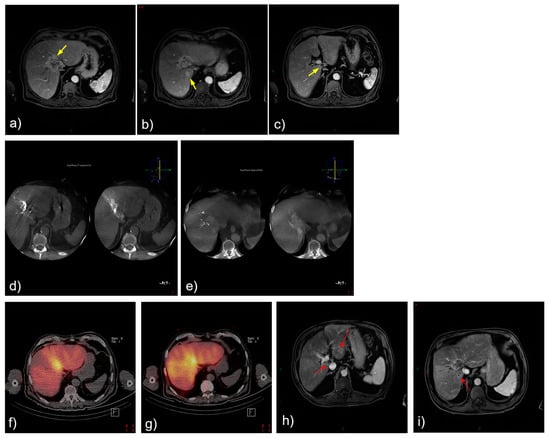

3.3. Selected Case 2 (Patient N 5, Figure 3)